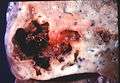

Pathology image of a lung abscess.

A subpleural abscess.